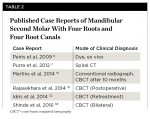

Table 1 is a tabulation of various studies representing data on morphological variation in mandibular second molar teeth in different populations.11-17,19,26-30 Table 2 lists various case reports of mandibular second molars with four roots.7,8,10,31-33

Cases of the following anatomical configurations have been reported: mandibular second molar with three separate independent mesial roots and one distal root; mandibular second molar with two mesial and two distal independent roots; and mandibular second molar with two mesial and one distal root with radix entomolaris.7-10 Although numerous studies have been undertaken, statistical data for various populations regarding incidence of four-rooted mandibular molars still has not been presented, except for 0.55% in the Israeli population.11-19

Typically, the number of mandibular second molar roots ranges from one to three.5 However, the incidence of four-rooted mandibular second molars is possible, although it is less than 1%.6 Thus, the four-rooted mandibular second molar observed in the present case seems to be a rare developmental anomaly of the molar root form.

In the present case report a rare morphologic variation of a mandibular second molar with four roots and four canals is evaluated with the use of CBCT. Orifice location to gain access is assessed through the observation of developmental root fusion lines on the pulpal floor. The successful nonsurgical endodontic treatment is described.